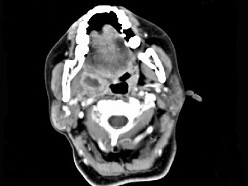

女,52岁,咽喉部疼痛半个月,伴低热,CT如图所示,可能诊断为()

A.咽旁脓肿

B.咽部神经鞘瘤

C.鼻咽血管纤维瘤

D.咽旁淋巴瘤

E.咽旁转移癌

[单选题]女,52岁,咽喉部疼痛半个月,伴低热,CT如图所示,最可能的诊断是()A.咽旁脓肿B.咽部神经鞘瘤C.鼻咽纤维血管瘤D.咽旁淋巴瘤E.咽旁转移瘤

[单选题,A2型题,A1/A2型题] 女,52岁,咽喉部疼痛半个月,伴低热,CT如图所示,可能诊断为()。A . 咽旁脓肿B . 咽部神经鞘瘤C . 鼻咽血管纤维瘤D . 咽旁淋巴瘤E . 咽旁转移癌

[单选题]女,52岁,咽喉部疼痛半个月,伴低热,CT如图所示,可能诊断为()A .咽旁脓肿B .咽部神经鞘瘤C .鼻咽血管纤维瘤D .咽旁淋巴瘤E .咽旁转移癌

[单选题]女,52岁,咽喉部疼痛半个月,伴低热,CT如图所示,可能诊断为()A . 咽旁脓肿B . 咽部神经鞘瘤C . 鼻咽血管纤维瘤D . 咽旁淋巴瘤E . 咽旁转移癌

[单选题]女,52岁,咽喉部疼痛半个月,伴低热,CT如图所示,最可能的诊断是()A . 咽旁脓肿B . 咽部神经鞘瘤C . 鼻咽纤维血管瘤D . 咽旁淋巴瘤E . 咽旁转移瘤